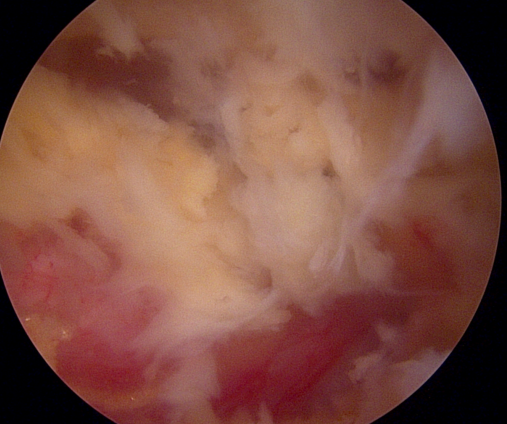

양방향 척추 내시경을 통한 다발성 척추 협착증의 치료 [온종합병원 척추센터 우영하 소장 ]

척추관 협착증은 척추관이 좁아지거나 협착되어 척수나 신경근을 압박하는 상태를 말합니다. 이런 경우, 양방향 척추 내시경이 매우 유용한 치료 수단이 될 수 있습니다.

- 계획: 양방향 척추 내시경은 미세한 카메라와 도구를 사용하여 척수와 주변 신경 구조를 정밀하게 시각화할 수 있습니다. 이를 통해 정확한 진단을 내릴 수 있으며, 각 환자에게 맞는 개별적인 수술 계획을 수립할 수 있습니다.

양방향 척추 내시경은 척추관 협착증과 같은 척추 질환의 치료에 있어서 현대적이고 효과적인 접근법 중 하나로 인정받고 있습니다.